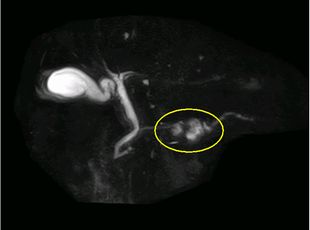

CT検査と同じような画像が得られますが、MRCP(MR 胆管膵管撮影)という特殊な条件での撮影では胆管や膵管の描出に優れており、膵臓がんによる胆管や膵管への圧迫の有無がわかります。

MRCP MIP画像(膵頭部嚢胞)